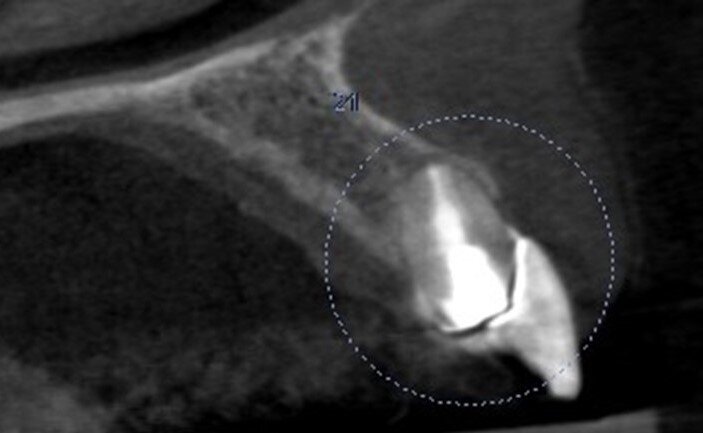

Una paziente di 53 anni si è presentata in studio con un incisivo sinistro fratturato a cui era stata più volte cementata una corona di ceramica (Figg. 1, 2). L’anamnesi e gli esami hanno evidenziato una buona salute sistemica e orale, un’occlusione ben equilibrata e nessuna abitudine al fumo. La tomografia cone beam (CBCT) e la radiografia periapicale hanno mostrato un riassorbimento radicolare esterno con inserimento nell’osso alveolare molto scarso, insufficiente per un adeguato posizionamento di un comune perno endocanalare (Figg. 3, 4). Considerando che il dente fratturato si trovava nella zona estetica, il paziente richiese un restauro nel modo più sicuro e più veloce possibile.

Fig. 4_Scansione CBCT pre-operatoria.